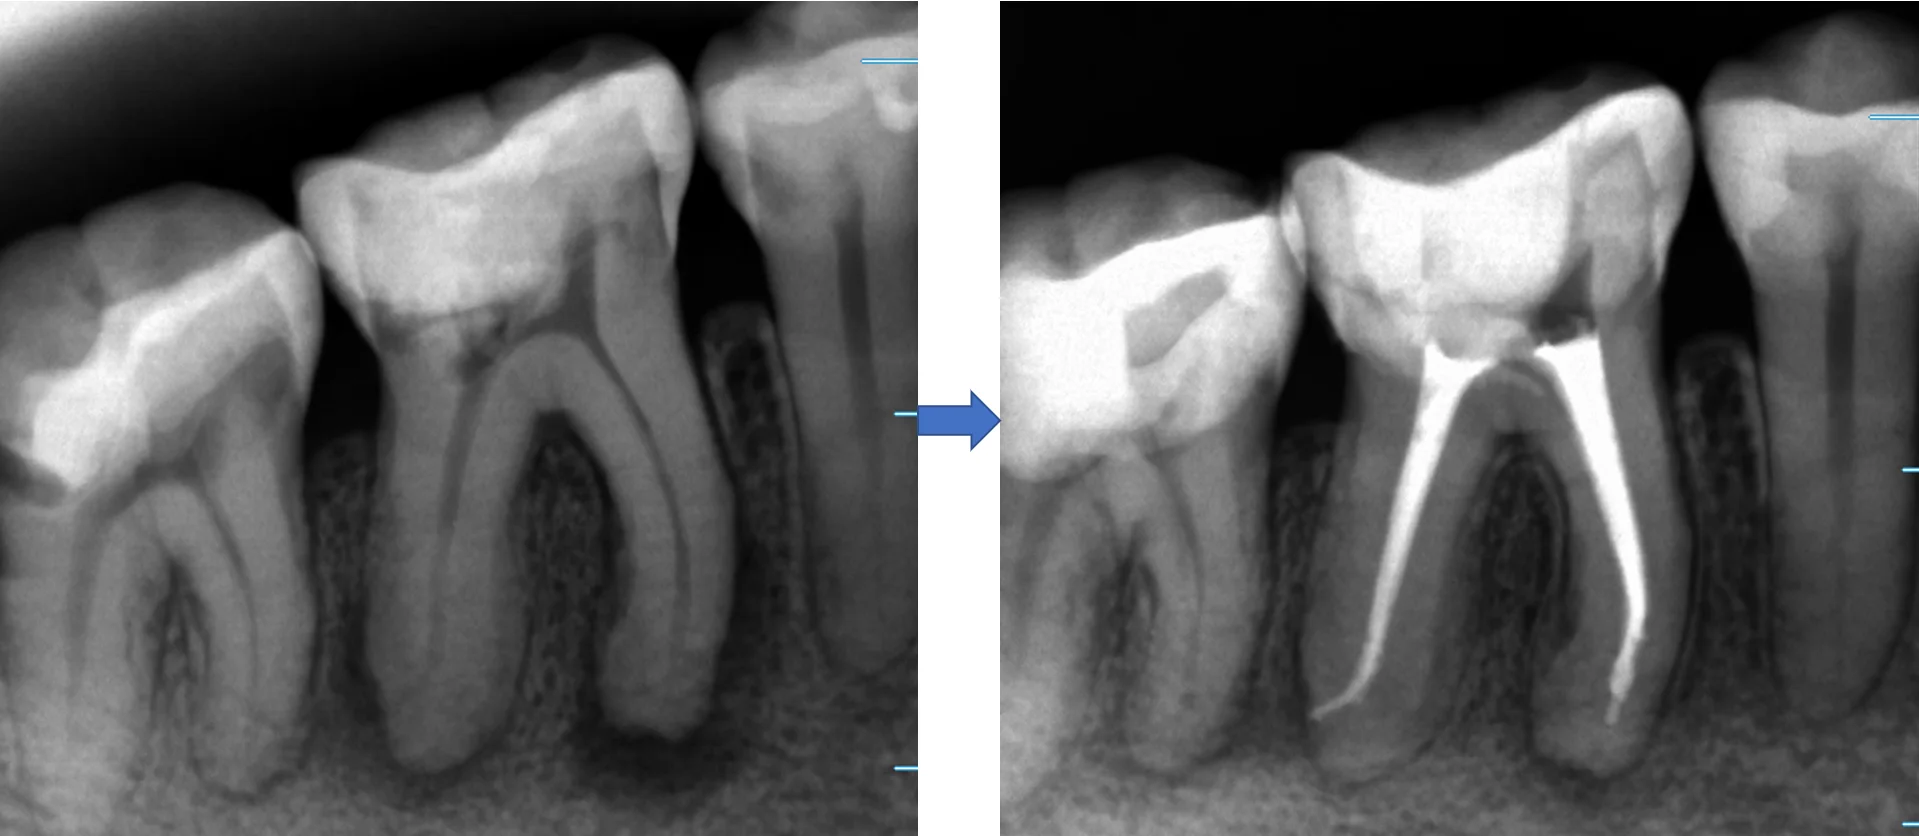

ちなみに、術前術後の変化がこちらです。

並べると、根の先の黒い部分が大分小さくなって、骨が出来てきているのが分かりやすいかと思います。

通常、3~4回程度で治療が完了するのですが、骨が出来るまでは半年から数年は掛かりますので、ここまで劇的に改善しているのが分かりやすいケースは少ないです。

今回は患者さんが比較的若く、骨代謝が活発な方だったので、短い治療期間でしっかりと良くなっているのが見えました。

通常は根管充填後半年から1年経ってから、もう一度レントゲンを撮らないと本当に治療が成功したかどうかは分かりませんので、今回のような場合は確実に上手くいっているのが分かるのでほっとしますね・・・(;^ω^)